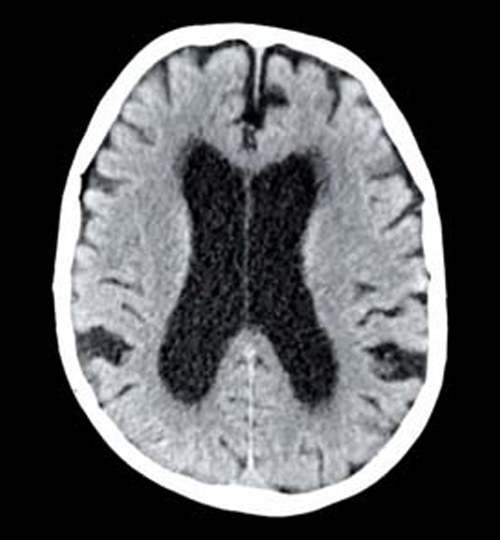

L’imagerie de référence est l’IRM cérébrale ; elle permet d’éliminer les diagnostics différentiels et d’obtenir une analyse morphologique et vélocimétrique.

Le signe le plus important est la ventriculomégalie objectivée par l’indice d’Evans (rapport entre le diamètre interne maximal des cornes frontales et le diamètre interne maximal du crâne, sur la même coupe axiale) [fig. 1].

Des sillons de la convexité médiane étroits, des dilatations focales des sillons de la convexité et un angle calleux aigu inférieur à 90 ° (fig. 1)5 constituent les autres signes radiologiques pertinents.

Complétant les séquences morphologiques, une IRM de flux permet de mesurer la vitesse et la pulsatilité du liquide céphalo-rachidien, qui sont élevées dans l’HPN.

Bien qu’il n’existe pas de critères diagnostiques définitifs, un score IRM a été développé il y a quelques années afin de regrouper les signes évocateurs ; il permet de prédire le pronostic après traitement (tableau 1).5

• L’IRM cérébrale montre une ventriculomégalie ainsi que d’autres signes de troubles de la circulation du liquide céphalo-rachidien.